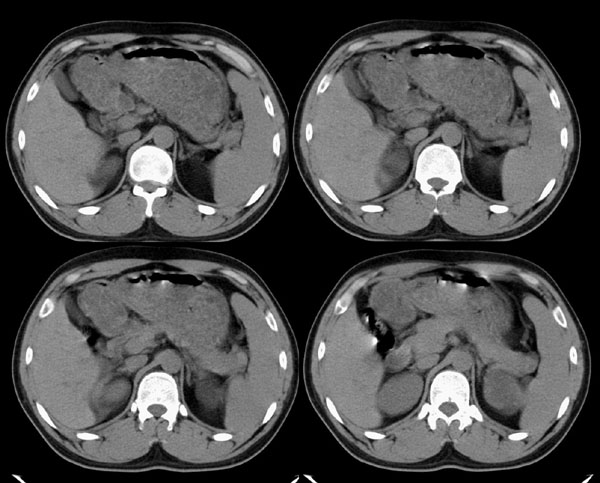

m29y平常体健,无明显不适。单位体检时发现左肾区病变。来我院作ct如下(病人不做增强):

左肾区囊肿冠、矢状重建: